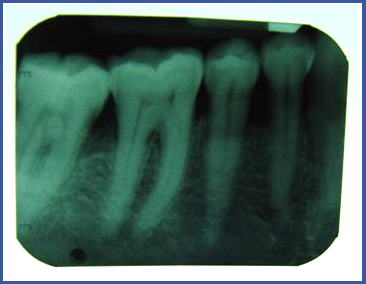

2.צילום פריאפיקאלי (PERIAPICAL)

זהו צילום בודד שנעשה במרפאת שיניים ומאפשר לראות את כל השן –כותרת והשורש וגם את הרקמה הקשה (עצם) סביב השורש.

צילום מסוג זה עושים בדר"כ בזמן טיפולי שורש , כאשר רוצים לבדוק האם ישנה דלקת סביב השורש או כאשר רוצים לבדוק את רמת העצם סביב השן.